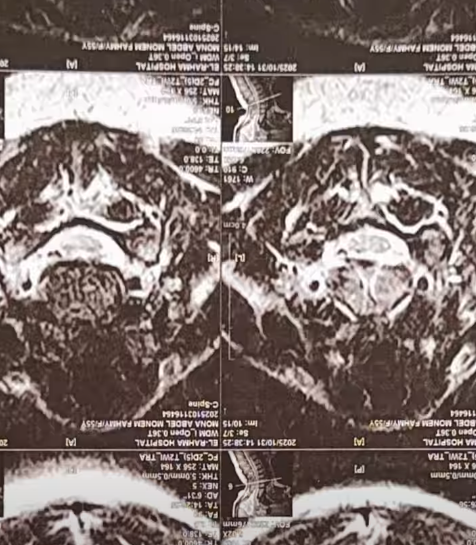

كشفت الإعلامية منى عراقي عن معاناتها في الفترة الماضية من أزمة صحية شديدة ، حيث أصيبت بمرض مناعي نادر مشيرة إلى أن الأطباء في مصر أكدوا لها أن المرض لا علاج له، وأنها ستضطر للعيش على العلاج الهرموني مدى حياتها .

وقالت منى عراقي في فيديو نشرته عبر حسابها على فيس بوك : الدكاترة في مصر قالولي جالك مرض مناعي ملوش علاج، واللي هنقدر نعمله إننا نكتبلك علاج هرمون هتعيشي بيه باقية حياتك.

وأضافت منى عراقي : قعدت 3 سنين أجرب كل حاجة علشان أخف، لحد ما قابلت سيدة ألمانية كانت مصابة بنفس المرض، وقالتلي عالجي السبب الأساسي للمرض مش الأعراض.